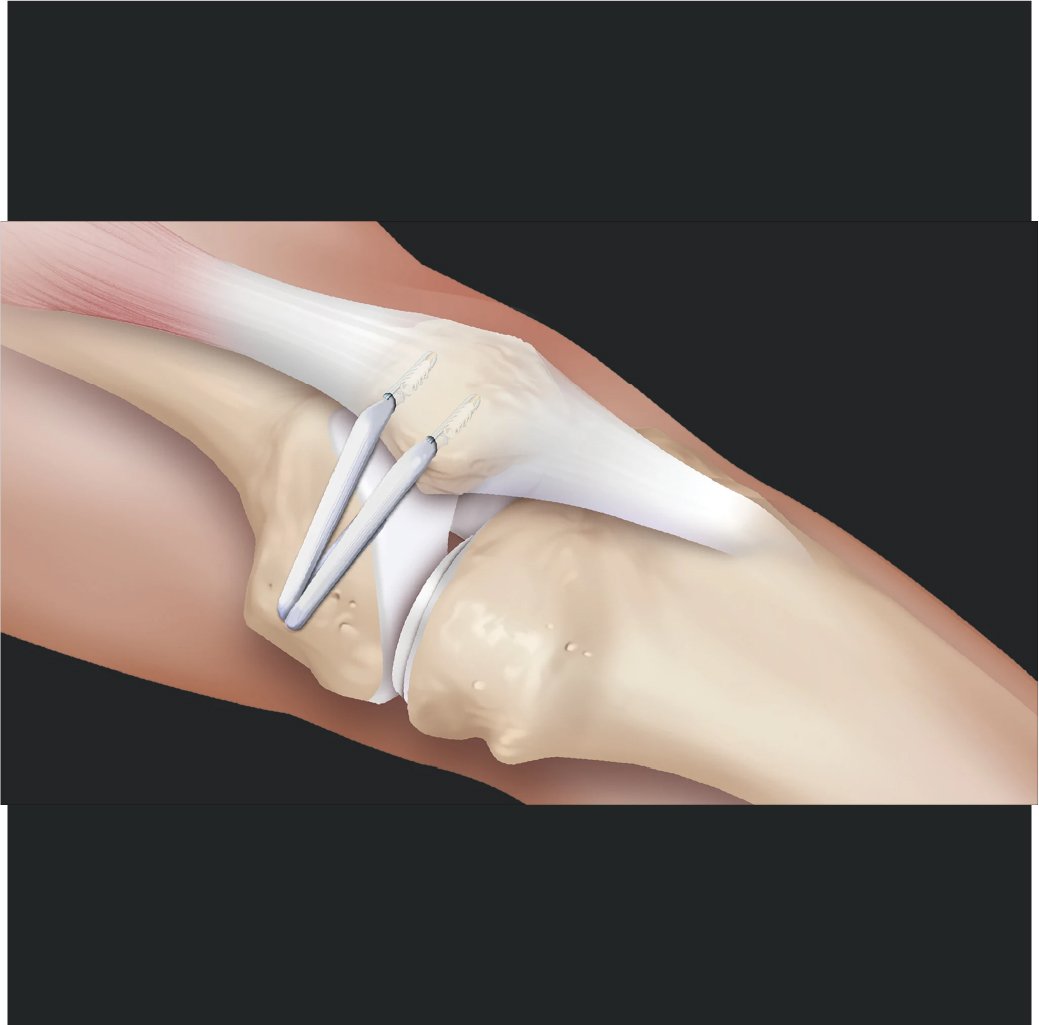

Knee preservation involves the use of non-surgical or surgical methods to maintain the integrity of a deteriorating joint. Its goal is to delay or prevent the need for joint replacement surgery, thus preserving natural joint function and mobility.